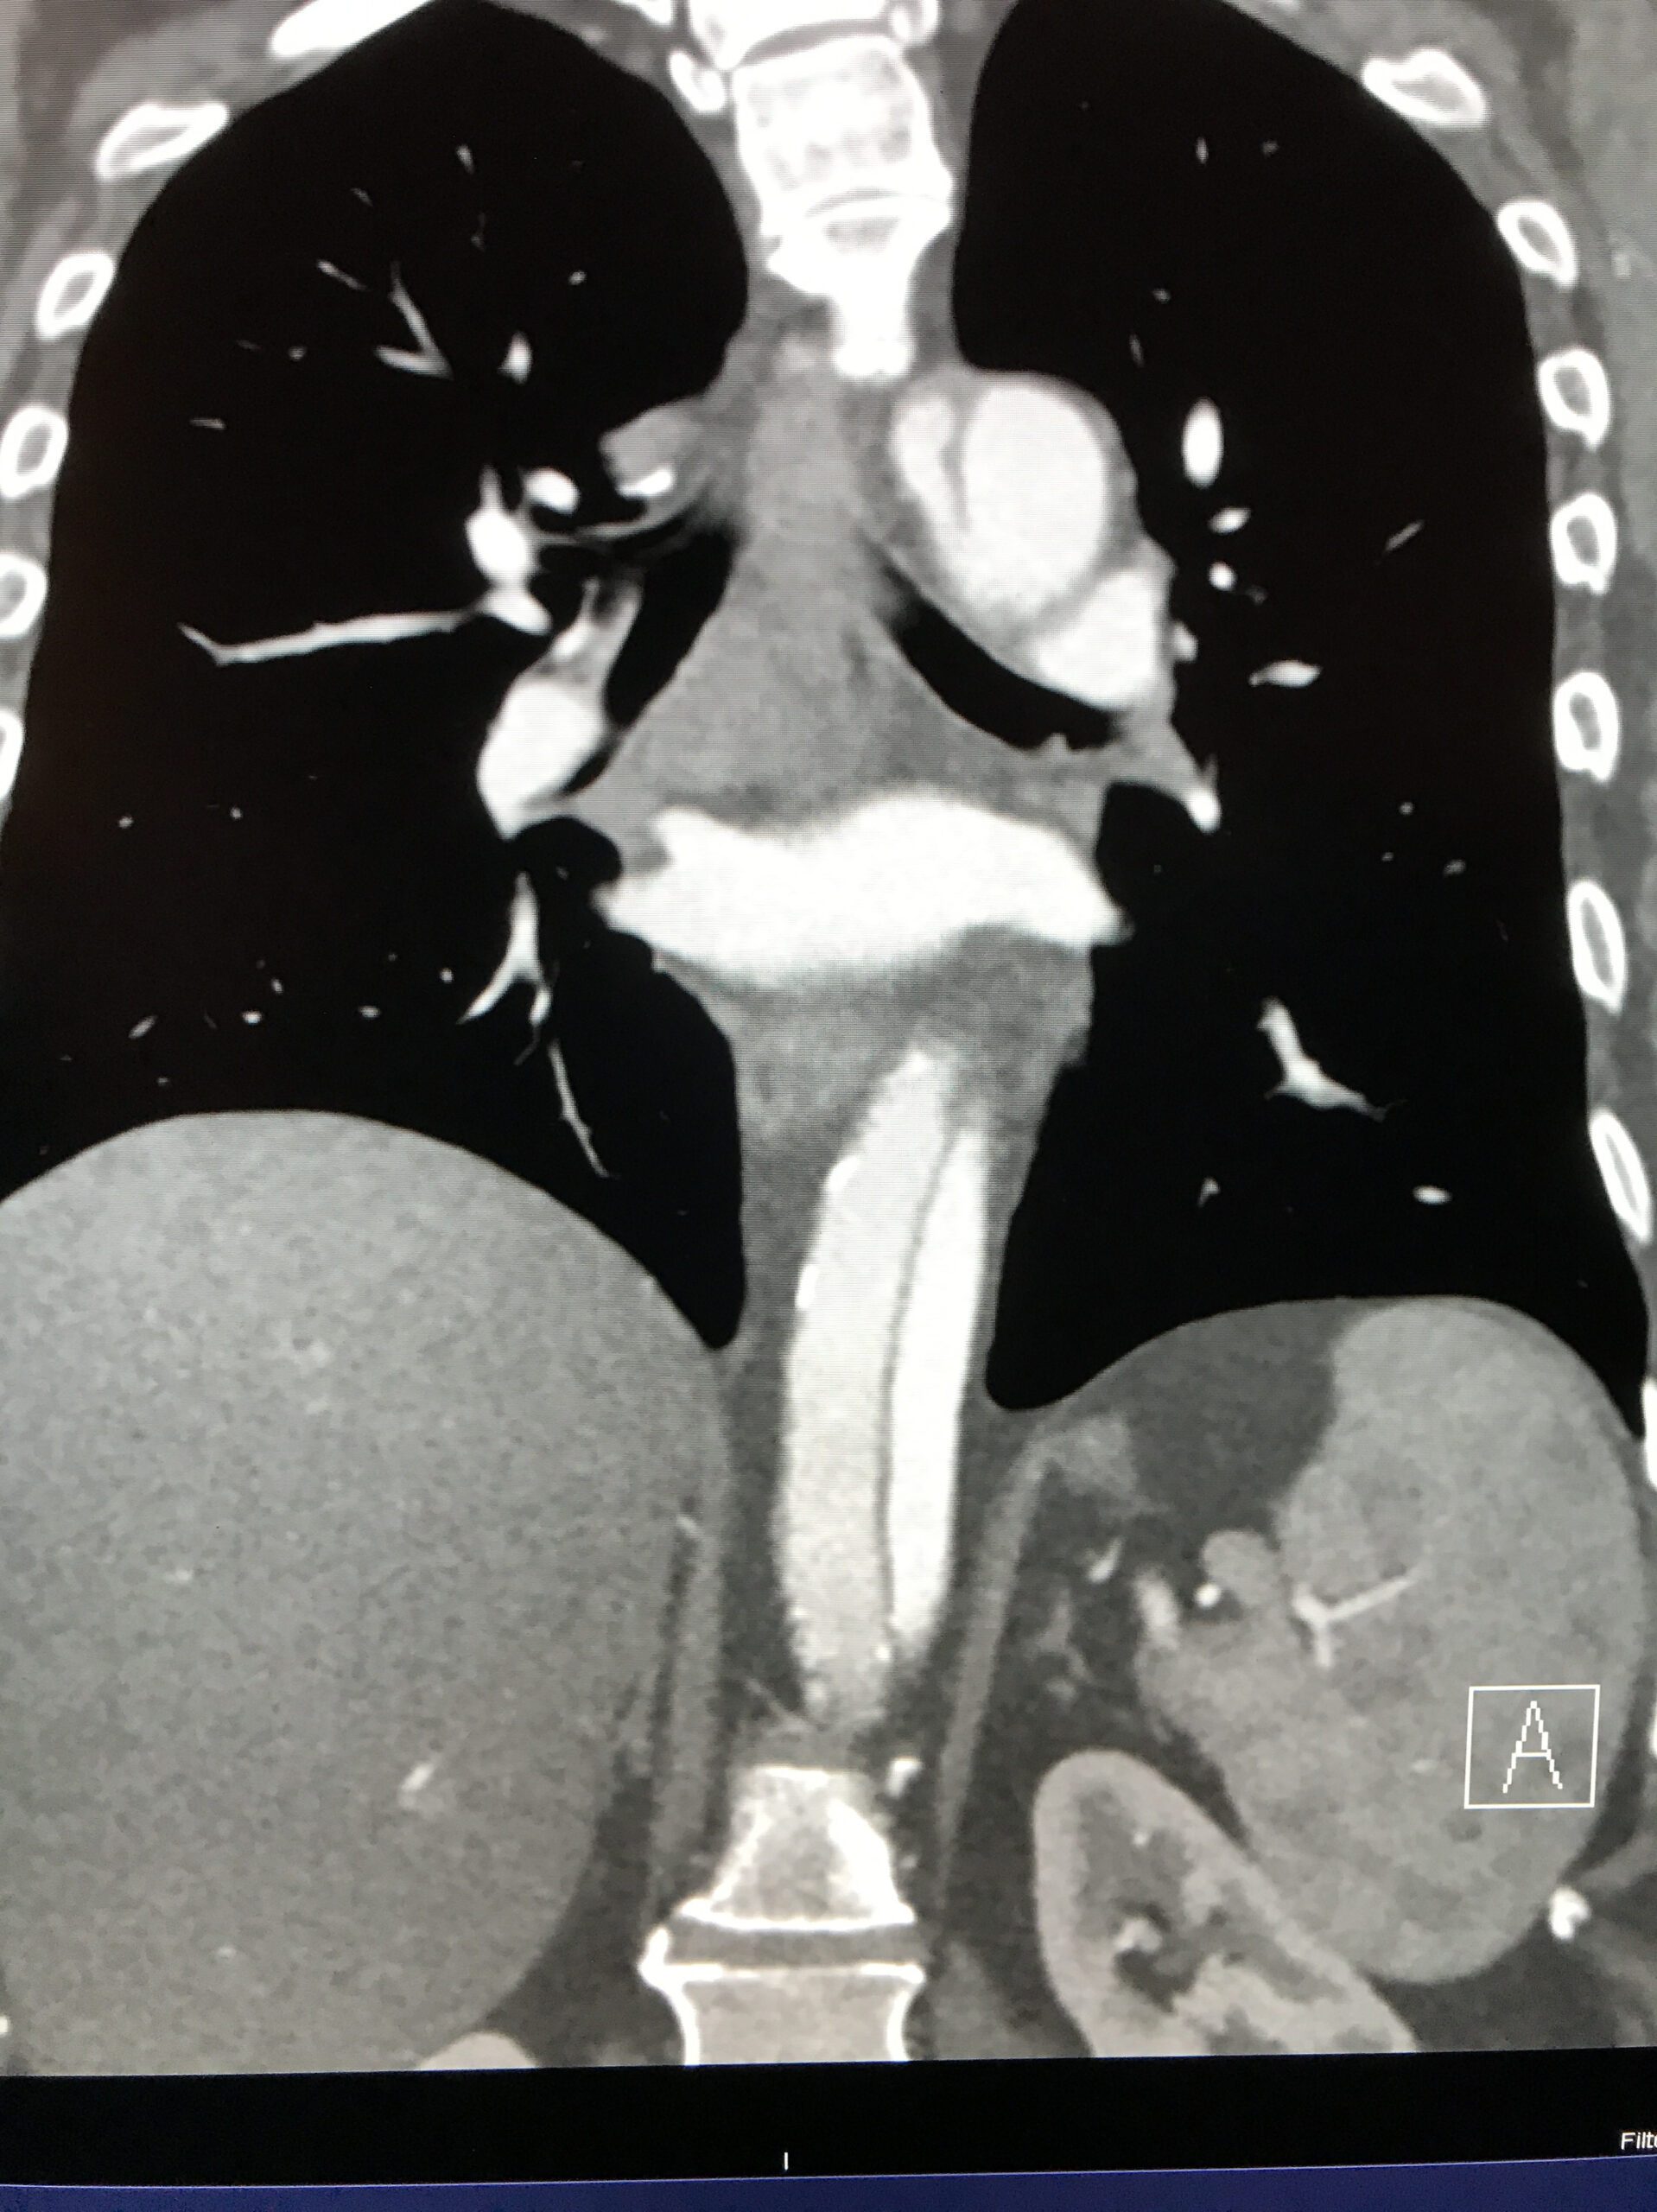

- A CT urogram is obtained and shows:

Image courtesy of Sam Ashoo, MD

Diagnosis: Acute Descending (Type B) Aortic Dissection

- The benefit of contrast: Though CT imaging has come a long way, the identification of vascular abnormalities continues to require the administration of intravenous contrast. As this case highlights, non-contrast imaging of the aorta relies on edema of surrounding structures or aneurysmal dilatation of the aorta to suggest abnormality. In the absence of either of these findings, no further analysis of the aorta can be made. The addition of contrast clearly highlights the intra-vascular space allowing for the correct diagnosis of this life threatening disease.